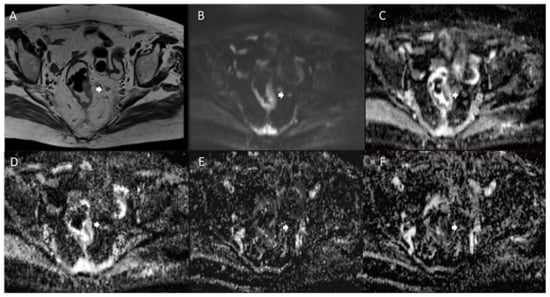

- Zhao, L.; Liang, M.; Yang, Y.; Xie, L.; Zhang, H.; Zhao, X. Value of Multiple Models of Diffusion-Weighted Imaging for Improving the Nodal Staging of Preoperatively Node-Negative Rectal Cancer. Abdom. Radiol. 2021, 46, 4548–4555. [Google Scholar] [CrossRef] [PubMed]

- Yu, J.; Dai, X.; Zou, H.-H.; Song, J.-C.; Li, Y.; Shi, H.-B.; Xu, Q.; Shen, H. Diffusion Kurtosis Imaging in Identifying the Malignancy of Lymph Nodes during the Primary Staging of Rectal Cancer. Color. Dis. 2018, 20, 116–125. [Google Scholar] [CrossRef]